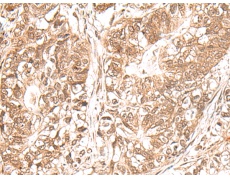

IHC positive control:

Human gastric cancer and Human ovarian cancer